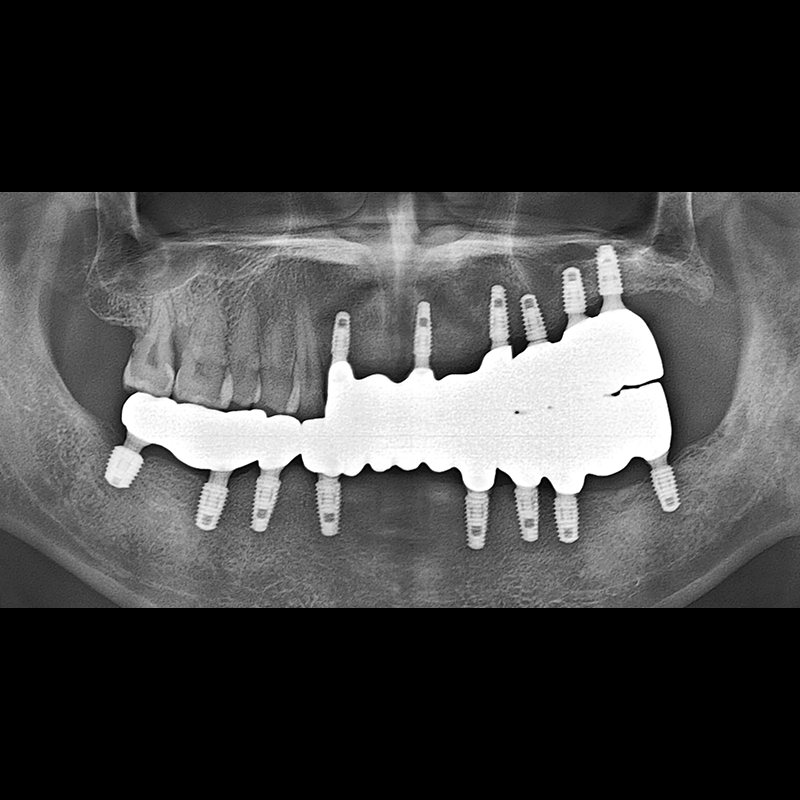

BEFORE AFTER

种植牙前后的照片 2025.05.30

在缺失的牙齿部分和难以挽救的牙齿位置植入了种植牙。